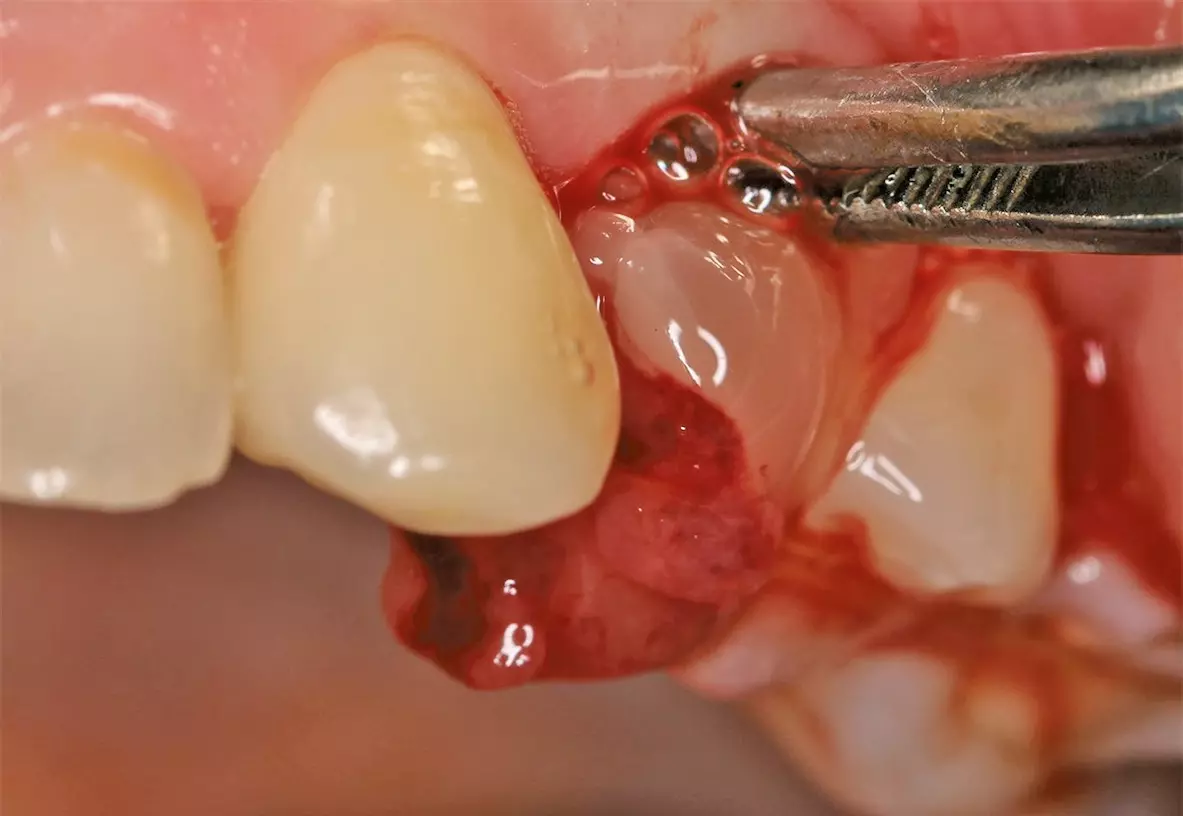

Nach ausführlicher Aufklärung und Beratung wurde die Extraktion des Zahnes 24 geplant. Zu diesem Zeitpunkt entschied sich der Patient gegen eine präventive Maßnahme zur Versorgung der Extraktionsalveole. Eine schonende Extraktion des Zahnes erfolgte komplikationslos unter gängiger Lokalanästhesie. Dabei konnte die vestibuläre Lamelle regelrecht erhalten werden (Abb. 2). Die Extraktionsalveole wurde mit einer Naht versorgt (Abb. 3). Ein Tag nach der Extraktion zeigt sich eine fibrinbelegte Wunde mit zeitgerechter und regelrechter Wundheilungsstatus (Abb. 4). Nach einer Woche wurde die Naht entfernt. Es zeigte sich zu diesem Zeitpunkt weiterhin eine fibrinbelegte Wunde mit einer okklusalen Mulde, die etwa 5 mm tief ist. Die Heilung war nach einer Woche also noch nicht komplett abgeschlossen (Abb. 5). In der frühen Wundheilungsphase berichtete der Patient beschwerdefrei gewesen zu sein. Drei Monate später stellte sich der Patient erneut vor mit dem Wunsch einen festsitzenden Zahnersatz zu bekommen. Die Extraktionsalveole zeigte eine vollständige Wundheilung und eine deutliche vestibuläre Knochenresorption (Abb. 6). Das Implantat konnte trotzdem eingesetzt werden und zeigt zum Zeitpunkt der Implantation eine adäquate Primärstabilität (Abb. 7). Nach drei Monaten wurde das Implantat freigelegt (Abb. 8) und anschließend mit einer Krone versorgt (Abb. 9).